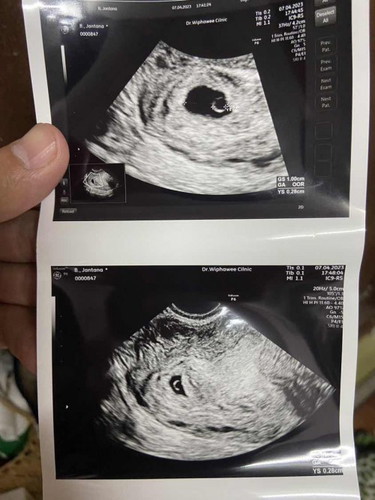

อัลตราซาวด์ 4-5week

เมื่อวันศุกร์ไปฝากครรภ์ และซาวด์มา คุณหมอบอกว่า เห็นถุงการตั้งครรภ์ อายุ ประมาณ 4-5 สัปดาห์ เห็นถุงไข่แดง แต่ยังมองไม่เห็นน้อง จึงนัดอีกที 18 เมษา มีใครเหมือนบ้านนี้บ้างคะ เอารูปซาวด์มาฝากให้ดูด้วยค่ะ ☺️